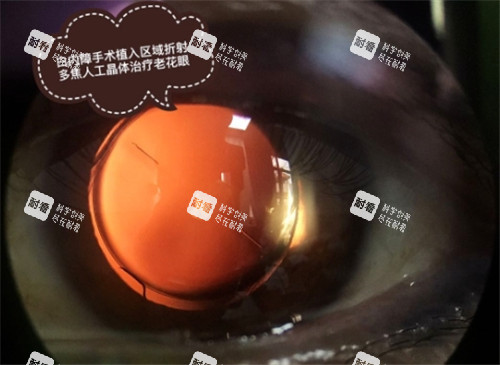

人工晶体是白内障手术的核心部件,它的质量直接影响术后视觉质量和生活便利性。

人工晶体分为单焦点、双焦点、三焦点和多焦点等类型。